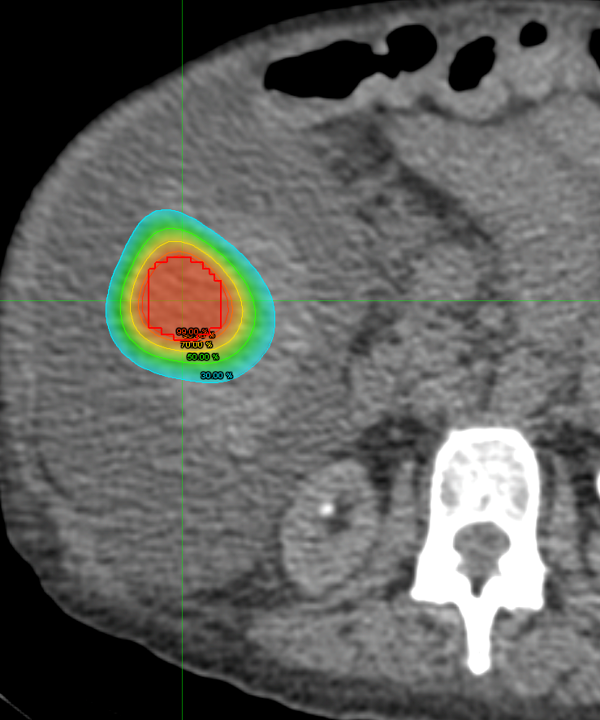

TheraSphere versus SirSphere Y90

There is growing literature suggesting that particle density is the underlying factor for disease control in patients with HCC undergoing Y90 treatment. We are doing a retrospective chart review of our institutional experience to add to the literature.